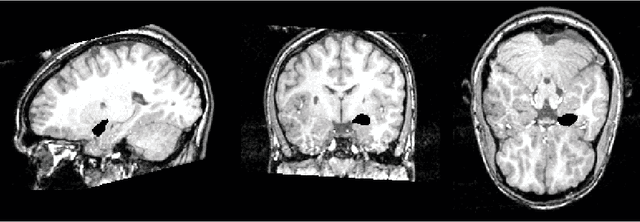

Abstract:This article is based on the first chapter of book Chung (2013), where brain and medical images are introduced. The most widely used brain imaging modalities are magnetic resonance images (MRI), functional-MRI (fMRI) and diffusion tensor images (DTI). A brief introduction to each imaging modality is explained. Further, we explain what kind of curve, volume and surface data that can be extracted from each modality.